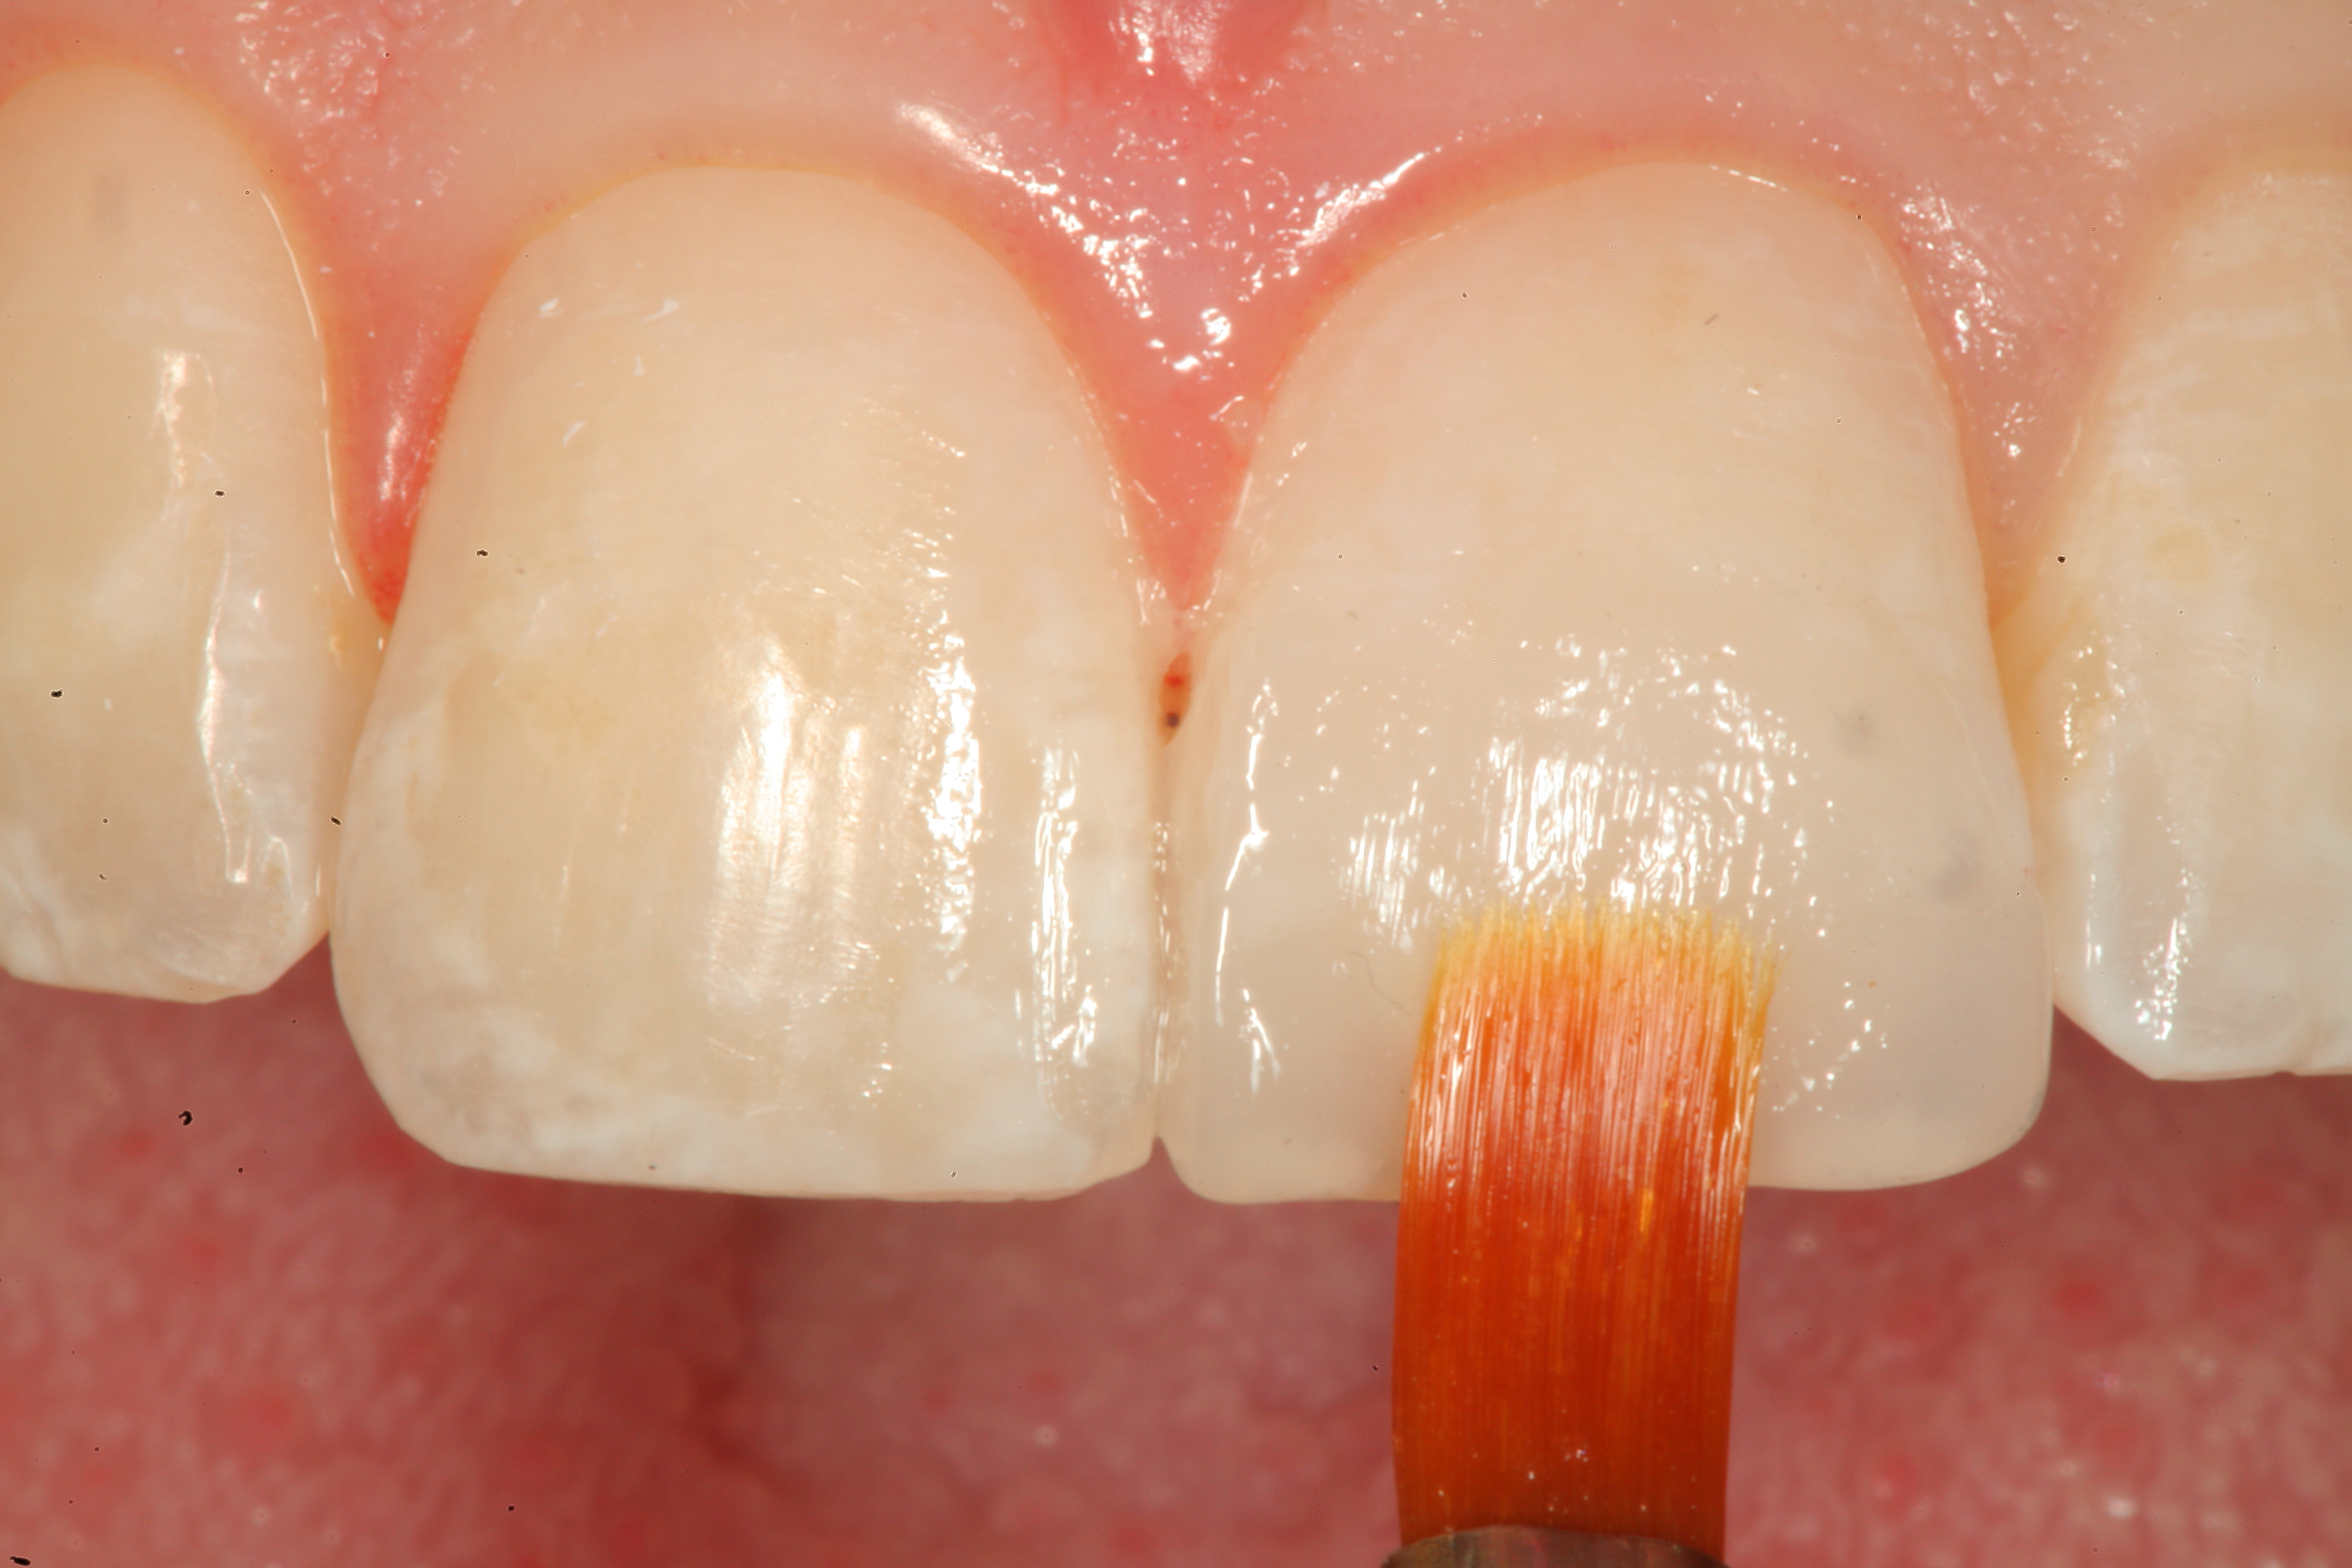

Fig 17. A white composite tint is placed with a sable brush to create a whitewashed appearance internally before placement of a clear enamel increment on top of it. This will allow the effect to show through in a similar fashion to those seen on natural teeth.

Figure 17

Fig 18. The clear enamel layer is smoothed with a sable artists’ brush before light-curing.

Figure 18